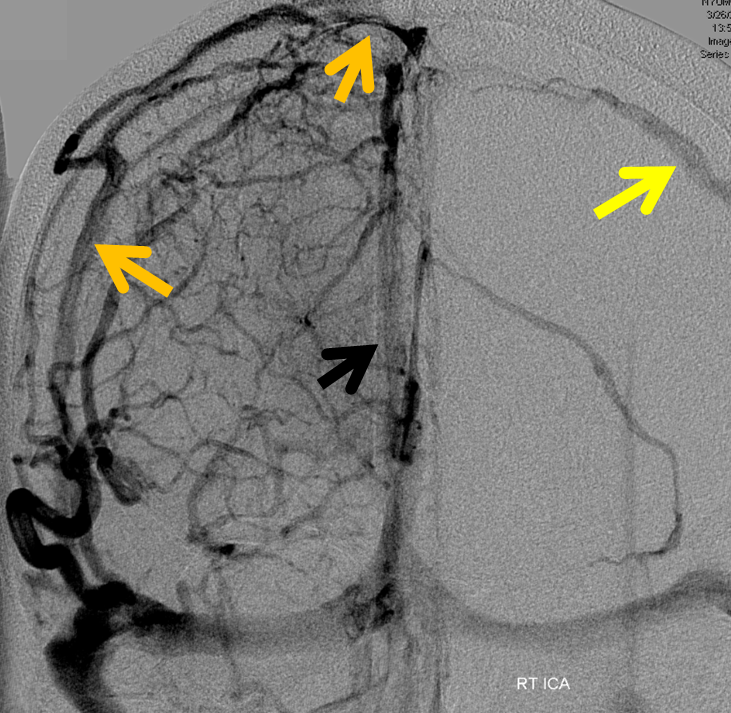

Below is a case of severe venous sinus thrombosis and secondary parenchymal venous infarcts

The explanation for the above tragic pattern is below. On the right, sigmoid and transverse sinuses are patent. However, the Labbe is hypoplastic, and majority of outflow used to go to the Trolard, into the now occluded SSS. There is no other effective way to go — the trolard tries to decompress via a left diploic vein, and convexity tries to access the deep venous system (which normally should not be well-seen in setting of hypoplastic right A1 segment). The left situation is much better, as well-developed superficial sylvian veins drain into the patent Cavernous Sinus. Thus, despite thrombosis of the left transverse and sigmoid sinuses, the left hemisphere is doing better, while the right one, which has patent transverse and sigmoid sinuses, is devastated.

Post venous thrombectomy — with limited results. Note presence of same left diploic vein as seen in right ICA injection, and connection between the distal superior sagittal sinus and the deep venous system via the inferior sagittal sinus.

Sagittal Sinus Thrombosis — collaterals.

All of the above anatomic knowledge can become very useful in evaluation of venous thrombosis. Numerous collateral pathways develop in this setting attempting to compensate for the loss. The most dramatic cases usually involve the largest channel — the superior sagittal sinus. In this case, a man presented with what initially was thought to be vasculitis-related brain hemorrhage. Subsequent workup led to an angiogram, where sagittal sinus thrombosis with extensive trans-cerebral and trans-osseous emissary vein collateral channels was seen. In retrospect, these findings were present on the patient’s earlier contrast MRI. “Venovibe” or other contrast-enhanced MR venograms can very sensitive, particularly when interpreted with the appropriate index of suspicion. Noncontrast 2-D time of flight MRV I consider to be next to useless as a problem-solving technique. Any thin-slice postcontrast T1 study is vastly superior.